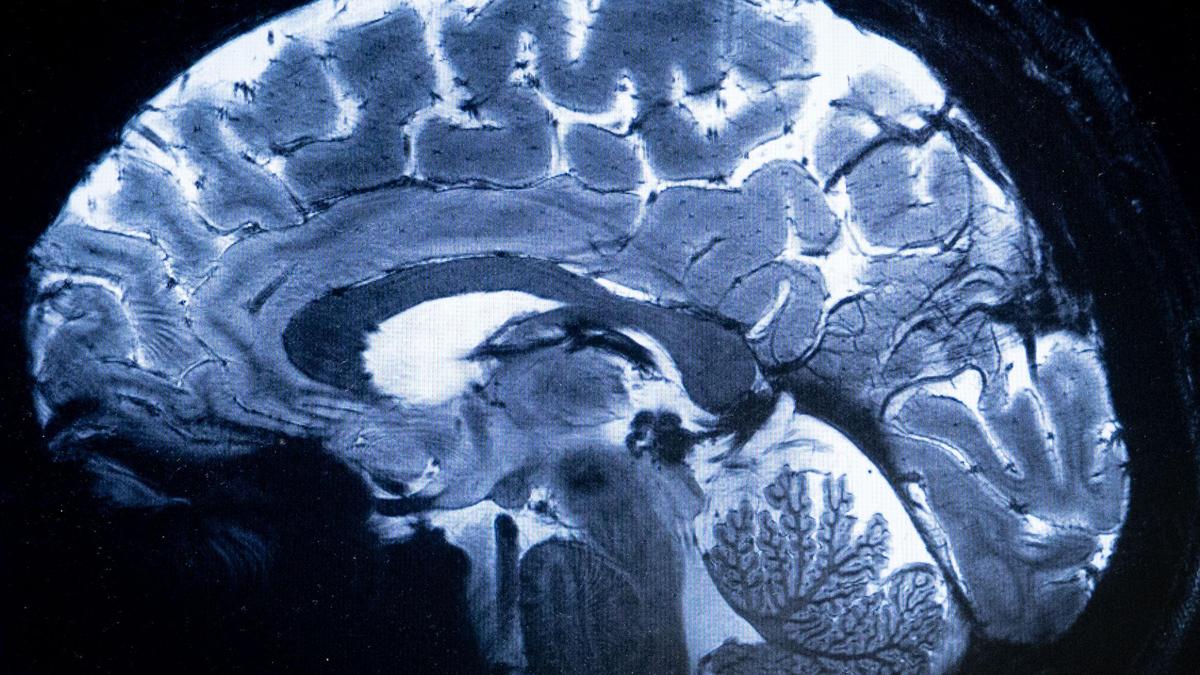

The study analysed the cerebral spinal fluid — a clear liquid surrounding and protecting the brain and spinal cord — of more than 100 schizophrenia patients and healthy people